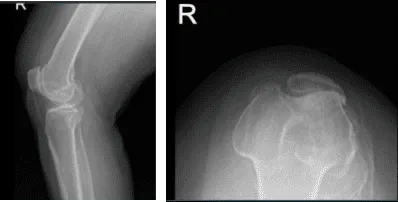

Aparte de esto, receté Relafen como antiinflamatorio. Los resultados de las radiografías y resonancias magnéticas se presentaron en la consulta. Los resultados de las radiografías mostraron cambios degenerativos osteoartríticos moderados y leves.

Resonancia magnética de la rodilla derecha

Impresión del resultado de la resonancia magnética es la siguiente: edema de médula ósea en la parte periférica anterior de la meseta tibial medial con ligera aplanamiento e irregularidad de la superficie articular; hay una impactación subcondral de bajo grado o fractura por estrés en cicatrización.

Desgarro complejo del cuerno posterior del menisco medial, incluyendo un colgajo meniscal desplazado que adentra en la raíz posterior y mide 1 cm de longitud. Artrosis patelofemoral severa. Artrosis femorotibial moderada. Derrame articular moderado.